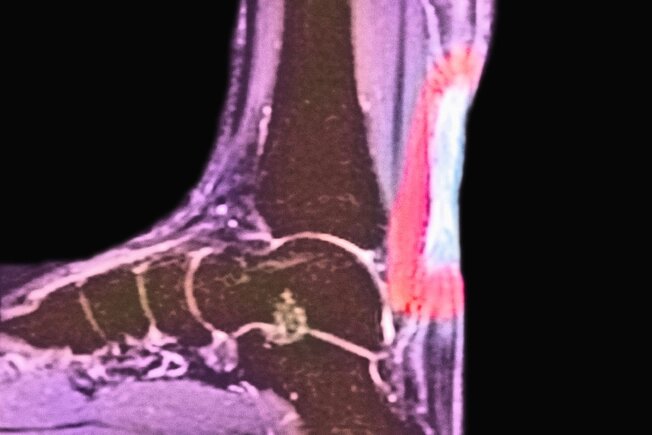

Tendinita lui Ahile

Tendonul lui Ahile este folosit pentru a flexa piciorul atunci când urci scările, stai pe degete sau alergi. Vârsta și scăderea aportului de sânge pot slăbi tendonul. Călcâiul sau spatele gleznei va doare atunci când apare problema. Odihna, frigul și analgezicele simple pot ajuta la combaterea umflăturilor. Nu ignora problema. Durerile severe pot necesita o intervenție chirurgicală pentru a restabili integritatea tendonului.